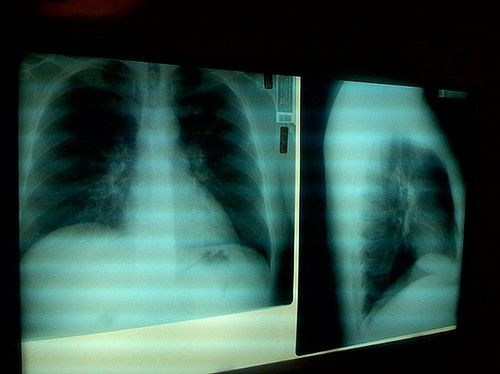

/ 6Zapalenie płuc

W niewyszczotkowanej jamie ustnej znajdują się nie tylko bakterie, ale także chorobotwórcze patogeny. Z każdym oddechem wdychamy je do płuc, gdzie mogą siać spustoszenie. Bardzo realnym zagrożeniem jest zapalenie płuc. Według badań naukowców z Flemish-Netherlands Geriatric Oral Research Group z Holandii regularne szczotkowanie zębów zmniejsza ryzyko zachorowania tą drogą o 40 procent.